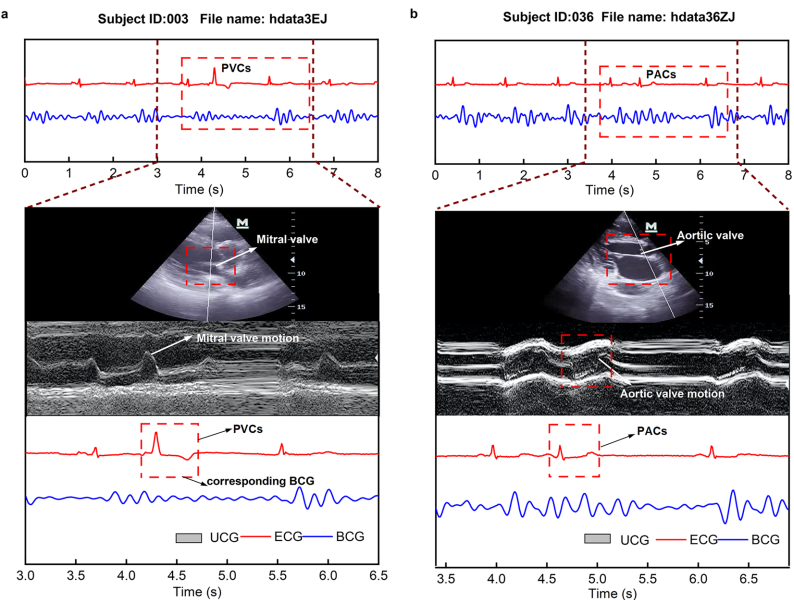

本研究针对传统心脏监测技术(如超声心动图)的局限性,开发了包含健康人群、心力衰竭(HF)及心律失常(心房颤动AF、室性早搏PVCs、房性早搏PACs)患者的多模态心冲击图(BCG)数据集。通过同步采集BCG、心电图(ECG)和M型超声心动图数据,结合增强奇异值阈值(ESVT)降噪算法,实现了心脏机械活动的无创连续监测。该数据集为开发基于BCG的心脏功能评估算法提供了重要资源,推动了心血管疾病远程监测的临床应用。

武汉理工大学与武汉大学中南医院的研究团队在《Scientific Data》发表了题为"A Multi-Pathology Ballistocardiogram Dataset for Cardiac Function Monitoring and Arrhythmia Assessment"的研究,建立了首个涵盖健康人群、心力衰竭(HF)及多种心律失常(AF、PVCs、PACs)的BCG数据集。研究同步采集了85名受试者的BCG、ECG和M型超声心动图数据,并开发了增强奇异值阈值(ESVT)算法进行信号降噪。结果表明,BCG与ECG的心率检测相关性达R=0.98,且在心律失常事件中能捕捉机械响应特征,为无创心脏监测提供了重要技术支撑。

关键技术包括:1)采用光纤传感床采集100Hz的BCG信号;2)同步AD8232模块记录ECG(100Hz)及M型超声心动图(Mindray M7 Expert系统);3)ESVT算法通过汉克尔矩阵构建和迭代奇异值阈值实现信号降噪;4)纳入武汉地区85例受试者(健康67例、心律失常15例、HF7例)建立多病理学队列。